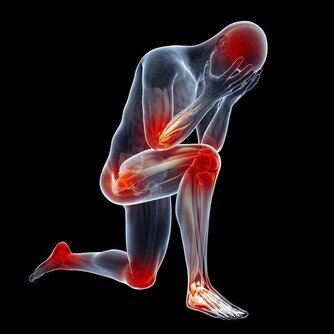

4. 誘發心臟病。牙垢久積所導致的牙周炎、牙髓炎會造成細菌毒素進入血液循環,最終危及心臟。

臨床上也顯示,經常患牙周炎、牙髓炎的人,患心臟病的幾率較常人高出許多。